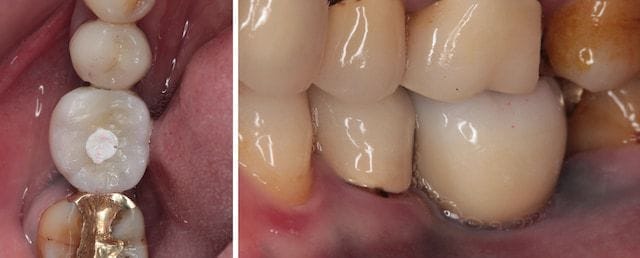

圖示:全瓷材質的牙冠(全瓷冠/全鋯冠)有一體成型、耐用、少瓷裂的優點

圖示:Mrs.Hsieh的全瓷冠植牙假牙採用螺絲固定設計,白色處為保留的螺絲通道位置

假牙的咬合面我們可以看到白色的暫時材料,就是保留的螺絲通道位置。